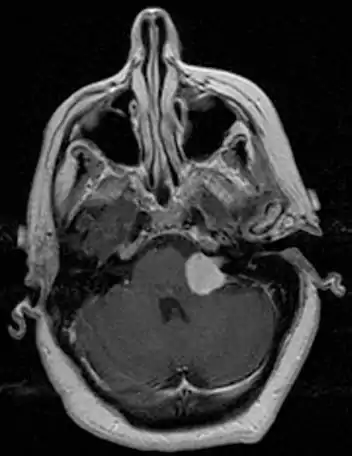

![]() | |

| Bilateral schwannomas in a patient with neurofibromatosis 2 | |

There have been cases of tumors that were actually asymptomatic until very large and at a critical stage. Tumor growth rates are highly variable: some small VSs (perhaps 50%) do not grow at all; some few grow for a time and then shrink; some appear dormant but suddenly grow rapidly. In general, although studies differ, VSs that grow are slow-growing at an average rate of 1.2 to 1.9 mm per year. IAC tumors that grow beyond 1.5 cm in diameter expand into the relatively empty space of the cerebellopontine angle, taking on the characteristic 'ice-cream-cone' appearance seen on MRIs. As 'space-occupying-lesions,' the tumors can reach 3 to 4 cm or more in size and infringe on the facial nerve (facial expression) and trigeminal nerve (facial sensation). Advanced hearing loss and spells of true vertigo may occur. Very large tumors are life-threatening when they press on the cerebellum or cause brainstem compression. Late symptoms of very large VS include headache, nausea, vomiting, sleepiness, mental confusion and eventually coma.[3][4]

MRI scan is the imaging of choice because it can more accurately differentiate the mass from other tumors such as meningioma, facial nerve schwannoma, epidermoid cyst, arachnoid cyst, aneurysm, and brain metastasis. MRI scan also helps in surgical planning and follow-up of the tumor after surgery.[17] VC is usually isointense on T1 weighted images, hyperintense on T2 weighted images, and enhances after given gadolinium contrast.[18]